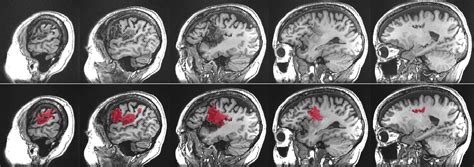

So, what is aphasia ? At its core, aphasia is a language disorder resulting from damage to the parts of the brain that control language. It’s not a problem with intelligence; people with aphasia are just as smart as they were before. Instead, their ability to process and use language has been impacted. Think of your brain as a super-complex computer. Language is one of its most sophisticated programs. When that program gets corrupted or parts of the hardware are damaged, it can lead to difficulties in understanding spoken or written language, or in expressing oneself through speaking, writing, or even gestures. It’s important to remember that aphasia can manifest in many different ways, depending on the location and extent of the brain damage. Some people might struggle to find the right words, others might have trouble understanding what others are saying, and some might experience a combination of these difficulties. It’s a spectrum, guys, and each person’s experience with aphasia is unique. The key takeaway here is that aphasia affects communication, not cognition. Someone with aphasia can still think, reason, and feel, but they might have a hard time expressing those thoughts or understanding yours clearly. We’ll delve deeper into the types of aphasia and their specific challenges as we go on, but for now, grasping this fundamental distinction is key to understanding the condition.

Let’s talk about causes of aphasia . Understanding what triggers this language disorder is super important for prevention and treatment strategies. The primary cause of aphasia is damage to the language-dominant areas of the brain. For most people, the left hemisphere of the brain is responsible for language functions. When these areas are injured, aphasia can result. The most common culprit, as we’ve touched upon, is a stroke . Strokes occur when blood supply to a part of the brain is interrupted, either by a blockage (ischemic stroke) or by bleeding (hemorrhagic stroke). This lack of blood flow deprives brain cells of oxygen, causing them to die. Depending on which part of the brain is affected, language abilities can be severely impacted. Another significant cause is Traumatic Brain Injury (TBI) . TBIs can happen from blows to the head, falls, or accidents. The widespread nature of the damage in a TBI can affect various brain functions, including language. Brain tumors can also lead to aphasia . Whether the tumor is malignant or benign, its growth can press on or invade brain tissue, disrupting normal function, including language processing. Brain infections , such as encephalitis (inflammation of the brain), can also cause damage to language areas. Lastly, neurodegenerative diseases are a cause, particularly Primary Progressive Aphasia (PPA). PPA is a group of brain disorders caused by specific types of dementia that target the brain’s language networks. Unlike other causes where aphasia might appear suddenly, PPA is typically a gradual decline. Each of these causes of aphasia presents unique challenges in terms of diagnosis, treatment, and prognosis. Knowing the cause helps medical professionals tailor the approach to managing aphasia , aiming to restore as much language function as possible and improve the quality of life for those affected. It’s a complex puzzle, and identifying the root cause is a critical piece.

Now, let’s get into the nitty-gritty: the types of aphasia . Because aphasia is caused by damage to different parts of the brain, it doesn’t just show up as one single problem. Instead, it’s classified into various types, each with its own set of characteristics. This classification helps speech-language pathologists (SLPs) understand the specific challenges a person is facing and develop targeted therapy. The two main categories are often fluent aphasia and non-fluent aphasia , with further subtypes within each.